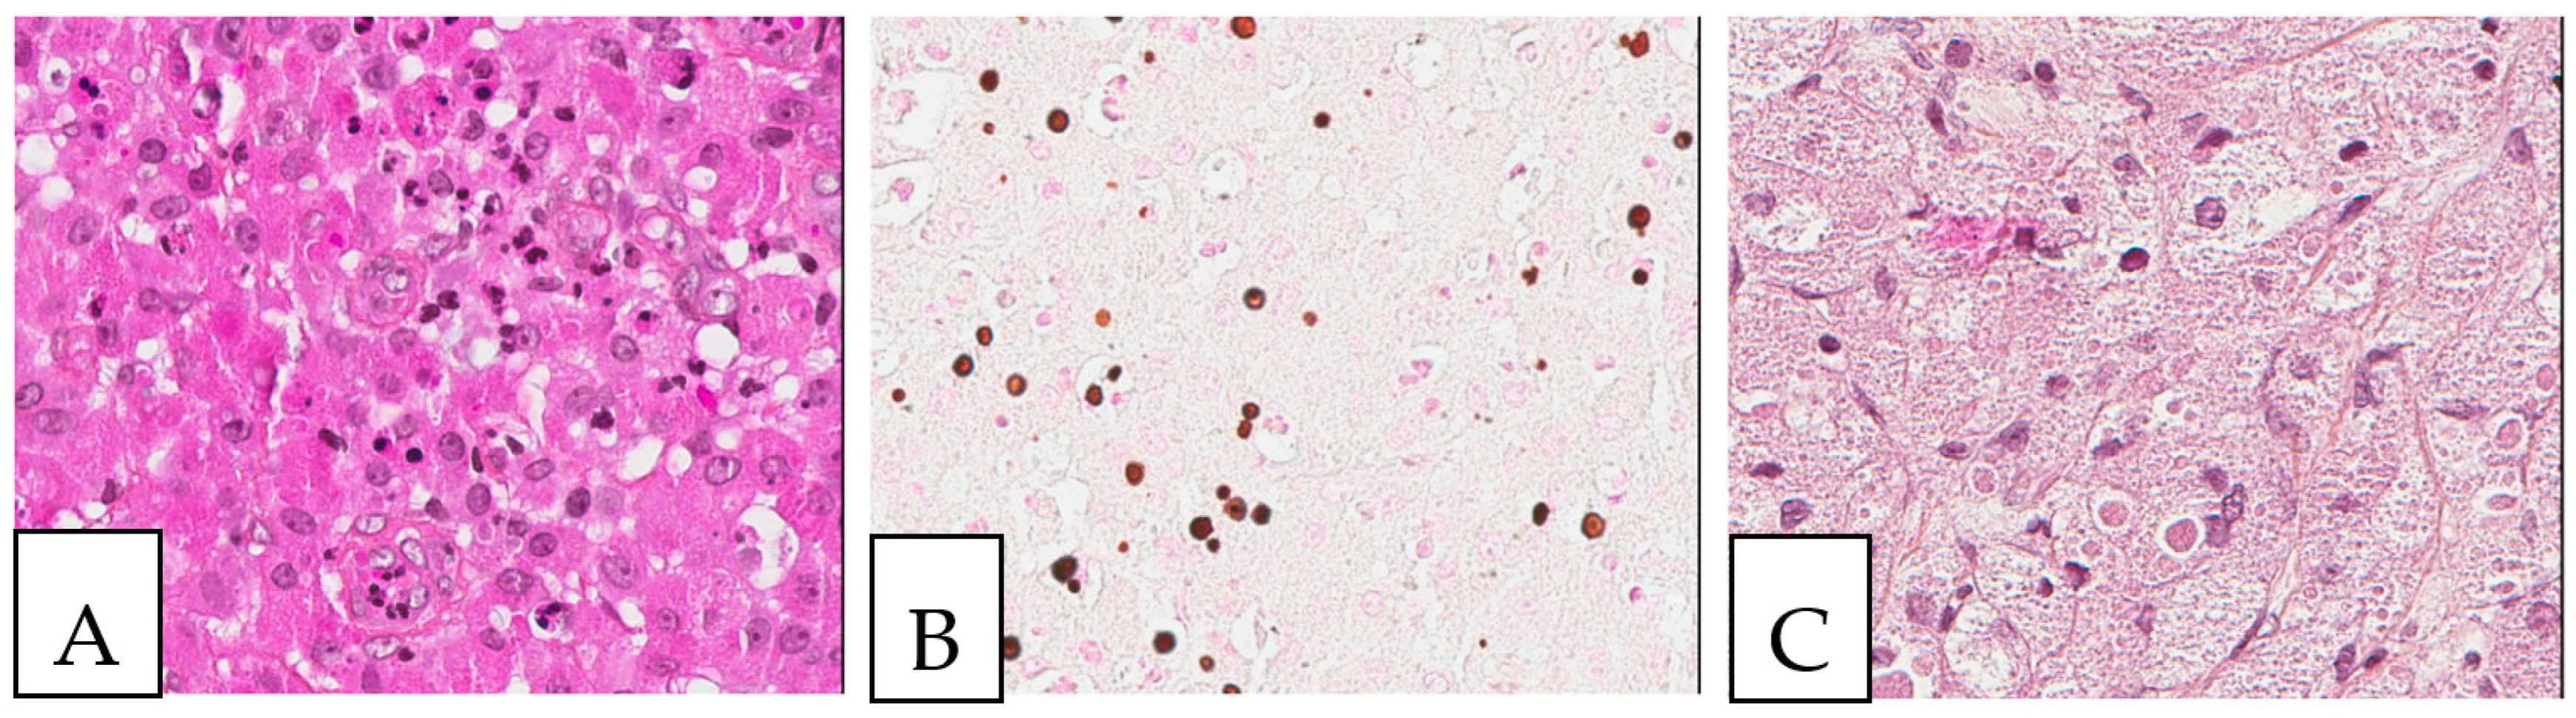

Figure 1.

(A,B) Crystal-storing histiocytosis is characterized by an accumulation of histiocytes with intracytoplasmic crystalline inclusions (arrows). (A,B) High magnification of samples from two different cases. (A) A 70-year-old male who presented with abdominal pain, cervical lymphadenopathy, and weight loss with colonic white mucosal elevations on endoscopy. (B) A 50-year-old male with a suspicious lesion of the cavum.

Detailed characteristics are presented in Supplementary Table S2. The size of the lesions ranged from 1 mm to 11 cm. A histopathologic examination is considered the gold standard for crystal-storing histiocytosis, as lesions are constantly composed of sheets of histiocytes that are filled up with crystalline needle-shaped to globular eosinophilic cytoplasmic inclusions (Figure 2). These inclusions are rarely accumulated within nearby plasma cells. In renal crystal-storing histiocytosis, eosinophilic cytoplasmic depositions can be seen in the tubular epithelium and in the glomeruli. This material can be positive or negative on PAS stains and typically negative on Congo red, Masson trichrome, acid-fast bacilli, Grocott–Gomori methenamine silver, Perls, Von Kossa, and Sirius red stains. The cells affected by crystal-storing histiocytosis are uniformly positive for anti-CD68 and anti-CD163 on immunohistochemistry, confirming their histiocytic nature. On the other hand, they are negative for anti-S100, anti-CD1a, anti-smooth muscle actin, anti-CD138, anti-langerin, anti-desmin, and anti-myoglobin. Importantly, due to the high clinical association of this disease with the monoclonal lymphoproliferative process with mostly monoclonal IgM kappa light chain restriction, it seems mandatory to investigate for the presence of lymphoma by asking for a lymphoma immunohistochemistry panel including CD20, CD79a, CD3, CD10, CD5, BCL2, BCL6, cyclin D1, CD23, and immunoglobulins light chains, either by immunohistochemistry or by in situ hybridization, as the first step to determine if it is a monoclonal or a polyclonal process. Typically, the crystals react positively to anti-kappa antibodies and negatively to anti-lambda antibodies in most cases of neoplastic crystal-storing histiocytosis. In contrast, crystals in the presence of non-neoplastic polyclonal crystal-storing histiocytosis will be react positively to both anti-kappa antibodies and anti-lambda antibodies. As the commonest accompanied pathology, multiple myeloma presents histologically with sheets or nodules of neoplastic plasma cells on bone marrow biopsy. There is typically an associated reduction in other hematopoietic cell lineages in cases of diffuse involvement. Interestingly, amyloid deposition secondary to the extracellular accumulation of monoclonal immunoglobulins in multiple myeloma can resemble crystal-storing histiocytosis, as it includes cells with an eosinophilic amorphous morphology. Unlike in crystal-storing histiocytosis, the amyloid disposition is positive for Red Congo stain with apple green Birefringent appearance. In addition, the deposition in crystal-storing histiocytosis is mostly within the histiocytes, whereas the amyloid deposition is typically extracellular, vascular, and perivascular. Immunohistochemically, the neoplastic plasma cells are positive for anti-CD138 and anti-MUM1 and present monoclonal immunoglobulin light chain restriction. Extranodal marginal zone lymphoma is characterized by sheets of small lymphocytes that usually reveal a distinct lymphoepithelial lesion in mucosa-associated lymphoid tissue organs such as the stomach. This lesion demonstrates sometimes a plasmacytic differentiation of the tumor cells. The neoplastic lymphocytes are positive for anti-CD20 and anti-BCL2 and negative for anti-CD3, anti-CD5, anti-CD10, and BCL6.

Figure 2.

Crystal storing histiocytosis. (A) Morphology of samples affected by crystal-storing histiocytosis, (B) CD68-positive histiocytes, (C) S100-negative lesion. This specimen is from the same patient described in Figure 1 (A) and was taken from a colonic white mucosal elevation.